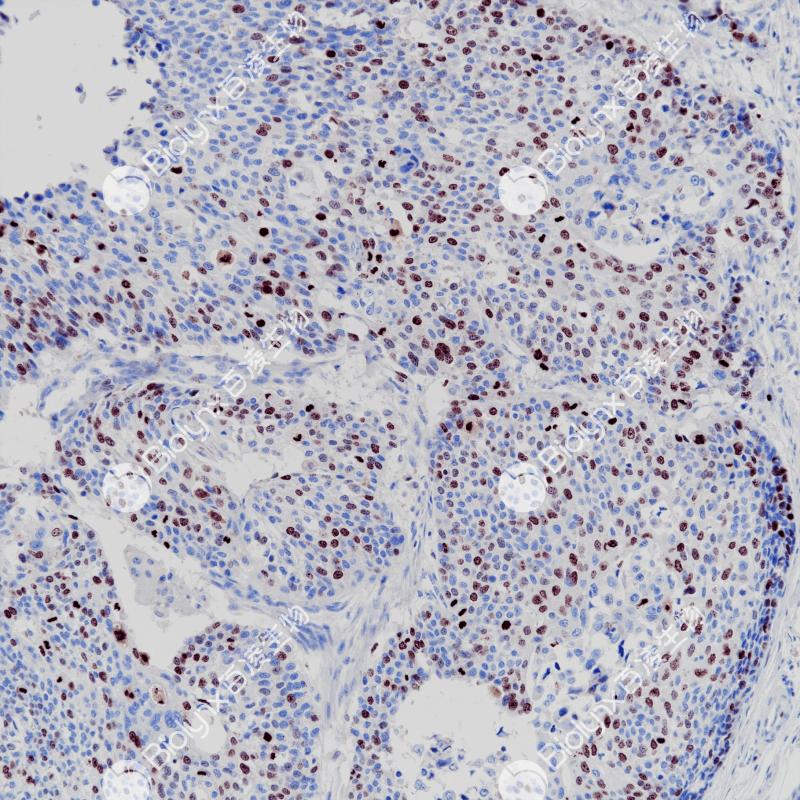

SATB2 重组兔单克隆抗体

SATB2是一种核基质附着区结合转录因子,在颅面、神经和成骨细胞分化中起重要作用。SATB2不仅表达于下消化道(阑尾、结肠和直肠)上皮,在发育中的皮质和脊髓神经元、成骨细胞、淋巴细胞、肾曲小管上皮细胞和脑神经元中也有表达。SATB2不仅是成骨细胞分化的标志物,也是结直肠癌的特殊标志物。SATB2在神经系统发育、骨骼发育和肿瘤细胞侵袭中发挥重要作用。

阳性对照

结肠癌

亚细胞定位

细胞核